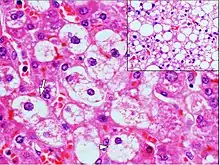

Histopathology of microvesicular steatosis, with foamy hepatocytes (two annotated by arrows), as opposed to macrovesicular steatosis (insert).

Microvesicular steatosis is characterized by small intracytoplasmic fat vacuoles (liposomes) which accumulate within hepatocytes.[9] It is associated with a wide variety of conditions, including alcoholism, drug toxicity of several medications, delta hepatitis (in South America and Central Africa), sudden childhood death, congenital defects of fatty acid beta oxidation, cholesterol ester storage disease, Wolman disease and Alpers syndrome.[10]